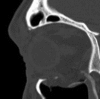

Orbital fractures are very common after facial trauma. The assessment of a patient with a suspected orbital wall injury includes a detailed oculofacial examination as well as radiologic imaging. Surgical repair with or without an implant may be indicated for diplopia, enophthalmos, or both. Cicatricial eyelid malposition is an iatrogenic complication commonly due to poor orbitotomy technique. Optimal repair involves direct exposure of the perimeter of the fractures' site through surgical planes that minimally scar the eyelids. A wide variety of implant options exist; however, thin, pliable, nonadherent materials such as nylon foil may offer several advantages. The authors describe the evaluation and management of orbital wall fractures.